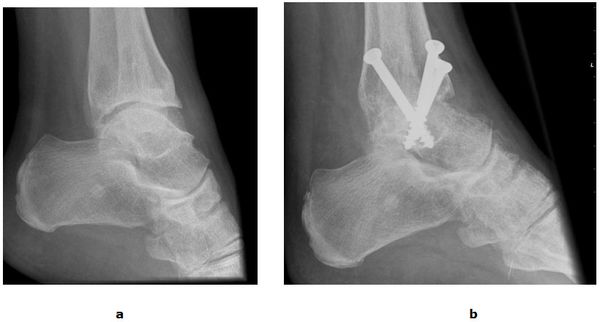

Die fortgeschrittene Arthrose des oberen Sprunggelenkes kann sehr schmerzhaft sein und die normale Fortbewegung stark beeinträchtigen. Die Versteifung des Gelenkes (Arthrodese) war Jahrzehnte lang die Therapiemethode der Wahl. Trotz einer Verbesserung der Schmerzsituation berichten Patienten über Probleme bei der Mobilisation. Hierunter fallen Schwierigkeiten beim Treppen steigen und beim aufstehen vom Stuhl. Im Laufe der Zeit können Schmerzen in überlasteten Nachbargelenken auftreten (Anschlussarthrosen) und das ohnehin hölzerne Gangbild weiter verschlechtern. Weitere Nachteile liegen in dem hohen Infektionsrisiko, der langen Rekonvaleszenzzeit (3 Monate Gips) und dem hohen Risiko einer Falschgelenkbildung (Pseudarthrose).

Abb.5: a Arthrose mit kontrakter Spitzfußstellung des oberen Sprunggelenkes. b Korrigierende Fusion mit drei Schrauben.

Die rekonstruktive Versorgung mit einer Sprunggelenksendoprothese ermöglicht dem Patienten im Vergleich zur Fusion eine wesentlich schnellere Mobilisierung mit Erhalt der Abrollvorgänge. 6 Wochen nach dem operativen Eingriff ist in der Regel das Laufen ohne Gips mit voller Belastung erlaubt. Dennoch eignet sich nicht jedes Gelenk für eine Endoprothese. In Fällen von hochgradigen Bandinstabilitäten oder erheblichen Knochenverformungen ist weiterhin die Fusion die Therapie der Wahl.